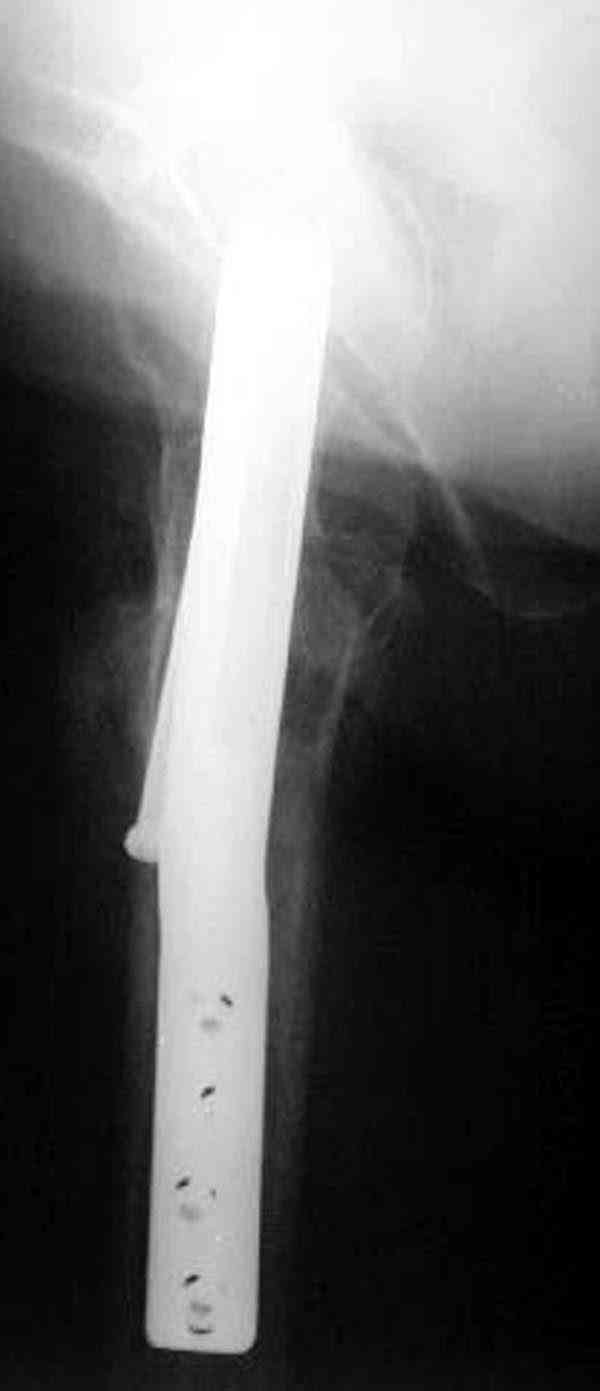

Уважаемый Антон! У меня было всего три клинических наблюдения, снимки были продемонстрированы на московской конференции. Количества этих снимков хватило для подачи заявки, а затем и получения патента на изобретение. В свое время РОСПАТЕНТ потребовал подтверждения методики клиническими наблюдениями. У одной из больных действительно произошла повторная травма, и произошел подвертельный перелом на стороне армированной шейки бедренной кости (см. снимки). Это подтвердило основную идею изобретения - была сохранена и головка, и армированная шейка бедренной кости. Но тут не обошлось безпроблем. Анестезиологи отказались давать наркоз, а провести остеосинтез под м/а пластиной и винтом DHS не согласилась больная. Дальнейшее лечение скелетным вытяжением. На контр. Рентгенограмме через 2 месяца признаки формирования костной мозоли. Повторных обращений двух других пациентов не было. Для более детальных исследований и выводов необходимо значительно большее количество клинических наблюдений. Такие исследования могли быть проведены в условиях клиник медуниверситета. Напомню, я работаю в травмотделении провинциальной городской больницы. Насчет экспертов страховых компаний, так пусть они выскажут свое мнение. Армирование кости - это плановые операции по желанию больного, какие здесь могут быть противоречия? На армирование все больные, к моему удивлению, согласились довольно легко и сразу, поэтому остеосинтез и армирование были проведены в течение одной операции. С уважением А.М.

Здесь случай перелома из-за ослабления латерального кортекса через 3 недели после операции на шейке. Шурупы были установлены под большим углом, слабый латеральный кортекс не выдержал нагрузку.